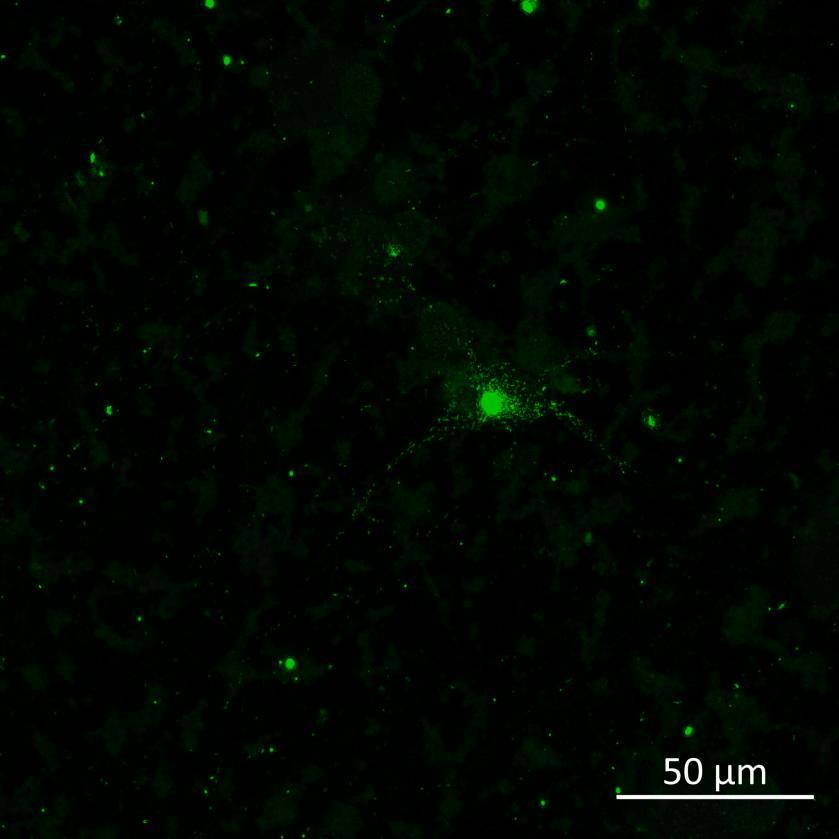

Phosphorylation and aggregation of native α-synuclein

• Isogenic control and early onset Parkinson’s disease SNCA A53T mutation neurons were exposed to α-synuclein PFFs with A53T mutation

• Neurons were fixed and labelled for α-synuclein phosphorylated at serine 129 (pS129)

• PFF treated neurons show Lewy body-like perinuclear aggregates of pS129 α-synuclein

• A53T mutation increases the proportion of pS129 positive neurons after PFF exposure